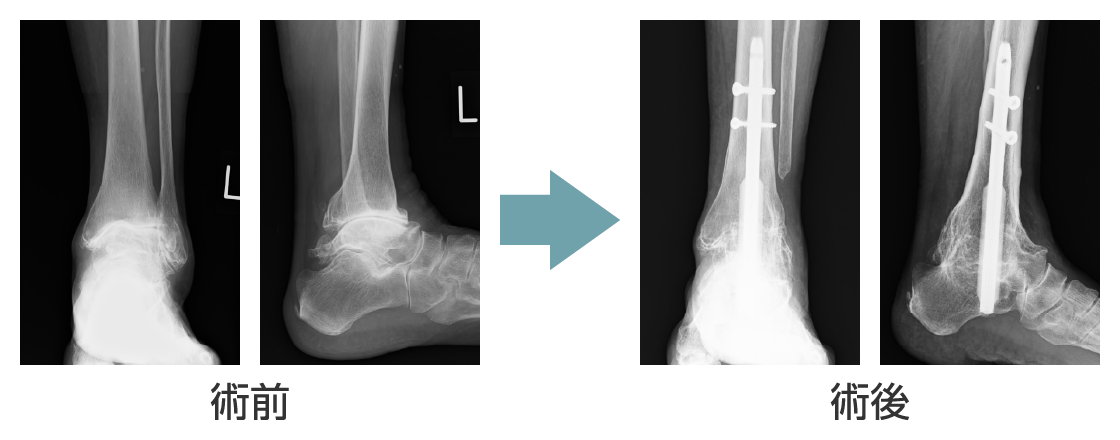

足関節固定釘の開発

私が大学病院勤務時代には、足首の関節(足関節)が壊れて歩行困難になったリウマチ患者さんに対しては成績の良い手術法はありませんでした。これを何とか解決しなければとの思いから足関節固定釘を考案致しました。この手術法は大変良好な成績が得られることから日本全国に普及し、現在まで全国で約5,600例に使用されてきました。関節リウマチに対する薬物治療の進歩により足関節の手術件数も減少してきていますが、それでも昨年も100例程に使用されていて、リウマチ患者さんのお役に立っています。